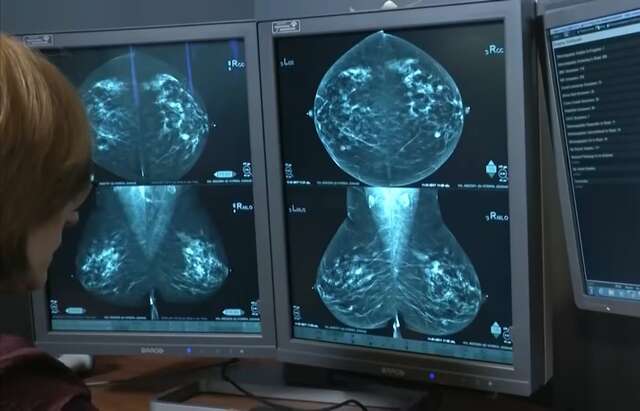

Ela alerta sobre a importância do diagnóstico precoce, por ser uma das principais ferramentas para aumentar as chances de cura do câncer de mama: “As mulheres não estão fazendo a mamografia. É a mamografia que permite a gente fazer diagnóstico precoce [...] Hoje a gente fala de 95% de chance de cura quando a gente acha pequenininho”, afirma.